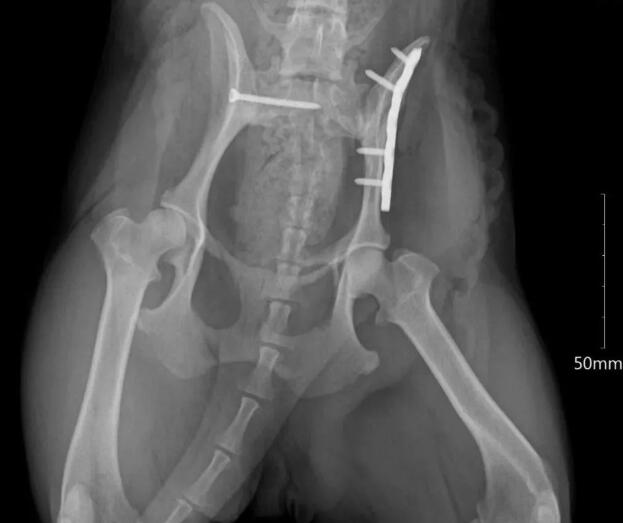

到了瑞鹏宠物医院后,医生哥哥仔细为我做了体格检查,血常规,生化及影像学检查。最终诊断为右侧荐髂关节脱位,左侧髂骨骨折。

术前X光片

隔天在小姐姐的陪同下,医生哥哥给我安排了手术。医院的唐蒙医师、王斌医师、单文倩医生自愿在下班时间参与了右侧荐髂关节内固定,左侧髂骨内固定手术,后肢掌骨由于医生判断可以自愈,就没做手术。

术后X光片